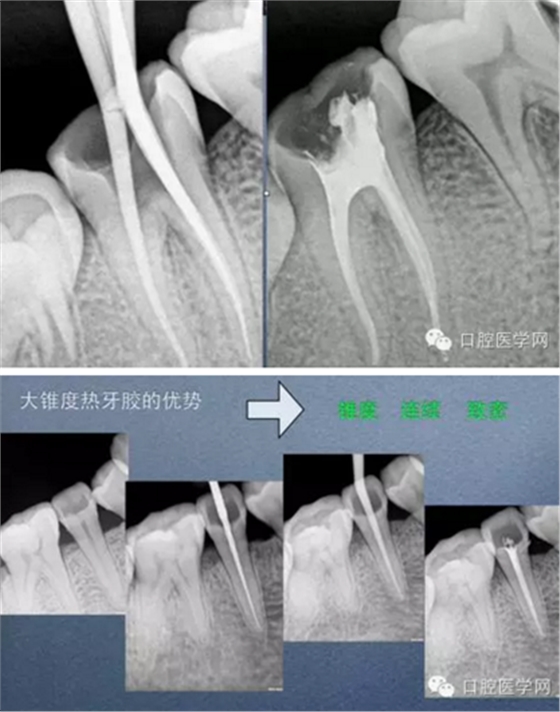

試尖(檢查是否恰填)

根充(從術(shù)后X光片可以看出根管充填完整,專業(yè)上叫恰充)

根充其實(shí)很簡單,只要前面的預(yù)備做好了,后面的充填就很順利,試尖恰好,AH樹脂湖劑+大準(zhǔn)度牙膠充填,平齊根管口將牙膠截掉,冷充的話就結(jié)束了。若要做熱充,將攜熱器頭對準(zhǔn)牙膠的中央,加熱3-4秒迅速壓入需要截?cái)嗟牟课唬缓蟮仁畮酌氪龜y熱器桿冷卻后再加熱1-2秒取出牙膠,最后將熱牙膠注入,邊注邊壓,嚴(yán)密充填,結(jié)束。暫封一周后冠修復(fù)。通過這樣的操作牙齒就不可能發(fā)生再次感染和疼痛了。

常用標(biāo)準(zhǔn):恰充,三維致密,流暢,錐度流暢一致。